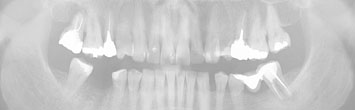

Clique nas imagens p/ampliar

Radiografia Panorâmica

A radiografia panorâmica, como o próprio nome diz, oferece ao cirurgião dentista uma visão ampla das condições dos dentes e osso alveolar, do osso da mandíbula e da maxila, bem como dos seios maxilares. Considerando que 2/3 dos dentes encontram-se imersos no osso alveolar da maxila e mandíbula a avaliação dos mesmos por meio de radiografias é imprescindível ao cirurgião dentista que busca um completo panorama da saúde bucal de seus pacientes.

A radiografia panorâmica não é o exame ideal para a avaliação de cáries, sendo muitas vezes indicada sua complementação com radiografias interproximais, técnica mais apropriada para observação de lesões de cárie.

• Posição dos 3ºs molares

* Muitos pacientes apresentam o 3º molar em posição não funcional ou incluso nos ossos da maxila e/ou mandíbula.

A radiografia panorâmica oferece ao cirurgião dentista a localização dos 3ºs molares, sendo indicada a complementação deste exame com tomografia computadorizada para maior detalhamento destes casos.